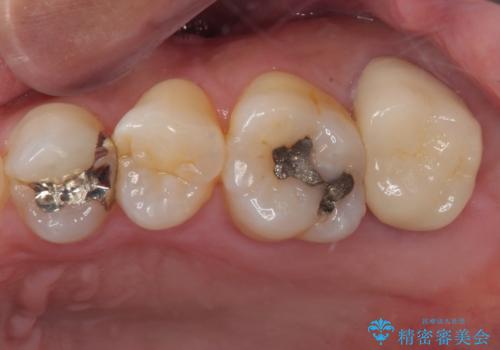

奥歯がしみる オールセラミッククラウンによる奥歯のむし歯治療